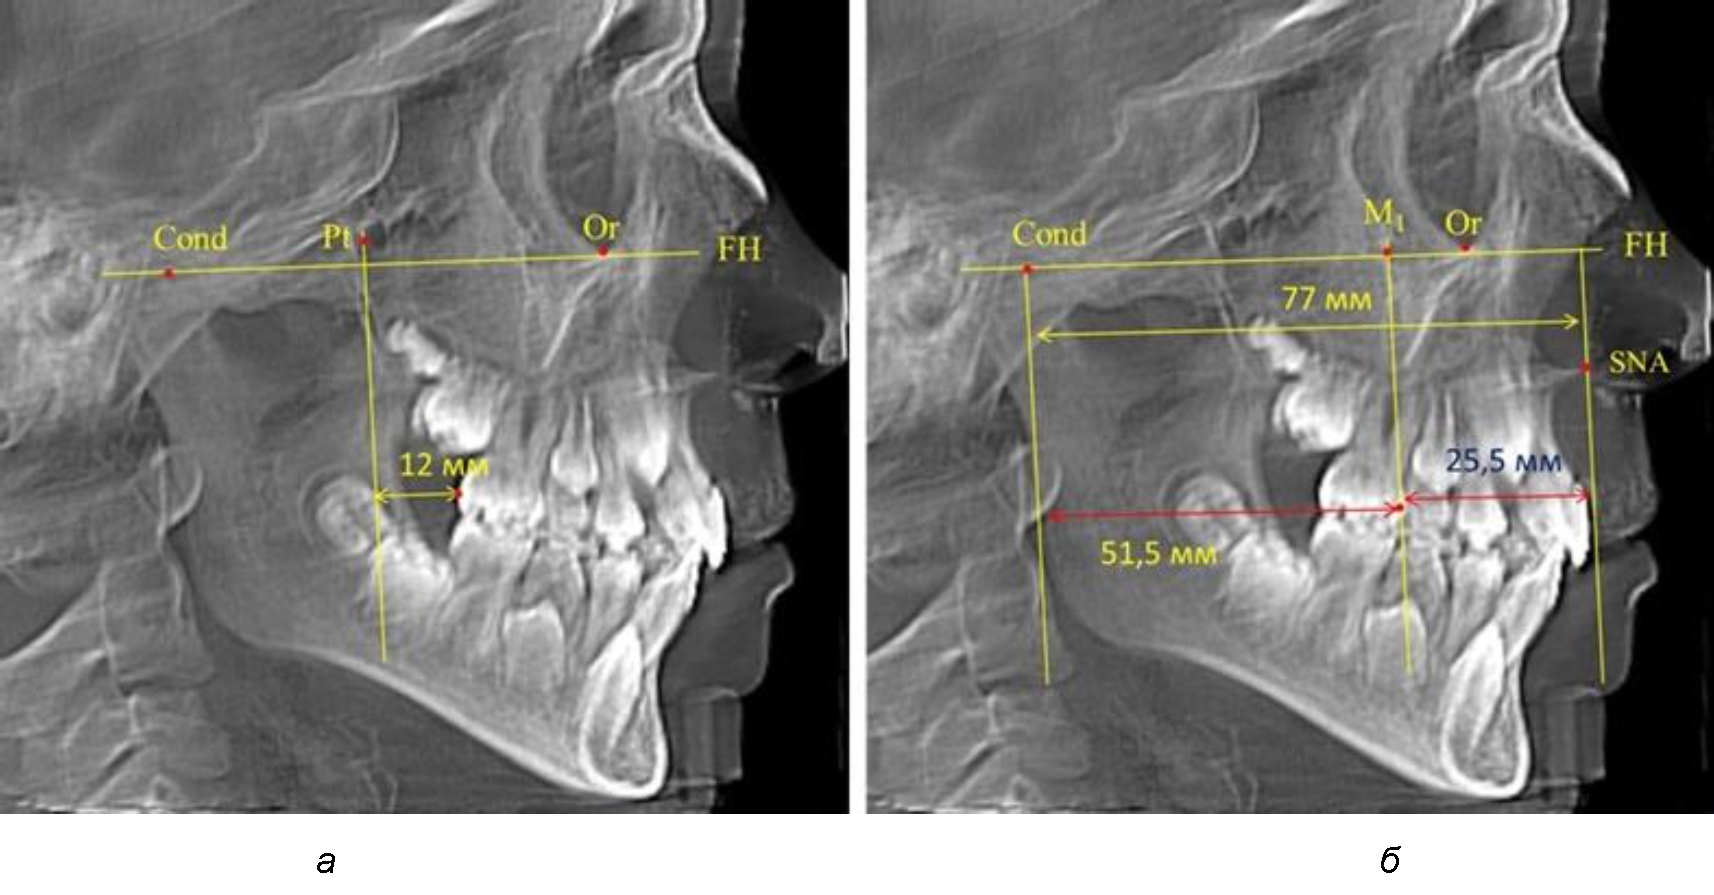

Рис. 1. Метод определения положения первых верхних моляров по Ralph E. McDonald (а) и по предложенному методу (б)

Анализ проведенного исследования рентгенограмм показал существенную вариабельность практически всех линейных показателей. У молодых людей с физиологическим прикусом постоянных зубов расстояние от крыловидной вертикальной плоскости PTV до дистальной поверхности верхнего первого постоянного моляра в целом по группе составляло (18,37 ± 3,62) мм. Обращает на себя внимание большая ошибка репрезентативности из-за разницы между максимальными и минимальными значениями.

Среди анализируемых рентгенограмм минимальное значение расстояния по методу R. E. McDonald было 12 мм, а максимальное достигало 25 мм, что, по нашему мнению, обусловлено вариабельностью сагиттального размера гнатического отдела лица.

Таким образом, для прогнозирования оптимального положения первых постоянных моляров наиболее целесообразным методом явилось использование относительного показателя, что подтверждено при анализе рентгенограмм с минимальными и максимальными значениями по методу R. E. McDonald.

Так, при расстоянии от крыловидной вертикальной плоскости PTV до дистальной поверхности верхнего первого постоянного моляра в 13 мм сагиттальный размер гнатического отдела был 82 мм. При этом отношение кондилярно-спинального расстояния к кондилярно-молярному размеру (54,5) было близким к коэффициенту 1,5, что представлено на рис. 2.